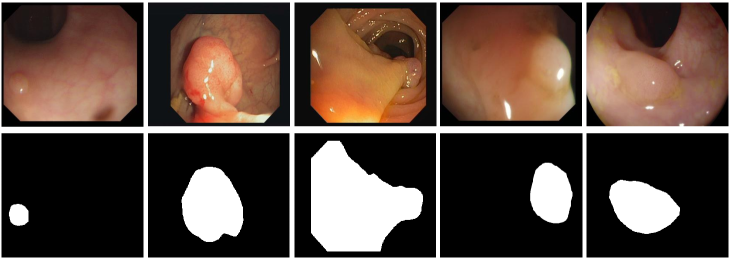

Although effectiveness has been achieved, due to variations in shape, size, and location, there is still considerable room to boost polyp segmentation. First, one of the major challenges is scale variation in polyp segmentation. As shown in Fig. 1, the first three columns show different scales and shapes of polyps. In this case, how to fully integrate the cross-level features and capture multi-scale information is still challenging. Second, as shown in the fourth and fifth columns of Fig. 1, the polyps have a similar appearance to the background, where the boundaries between the polyps and their surrounding mucosa are not sharp. Thus, how to effectively utilize the boundary information or incorporate edge-enhanced features into the decoder still deserves further exploration.

Fig. 2 presents the architecture of our EFA-Net. Specifically, the Res2Net pami20Res2net is adopted as the backbone to extract multi-level features for given images, denoted as . Then, the proposed EGM combines the low-level features (i.e., and ) and the high-level feature (i.e., ) to learn an edge-enhanced feature, which is further incorporated into the decoder. Besides, each feature is fed into the proposed SCM to extract the multi-scale features. Further, we utilize the CFM to integrate the cross-level features to fully exploit the local and global contextual information. Finally, our decoder produces multiple side-out segmentation maps .